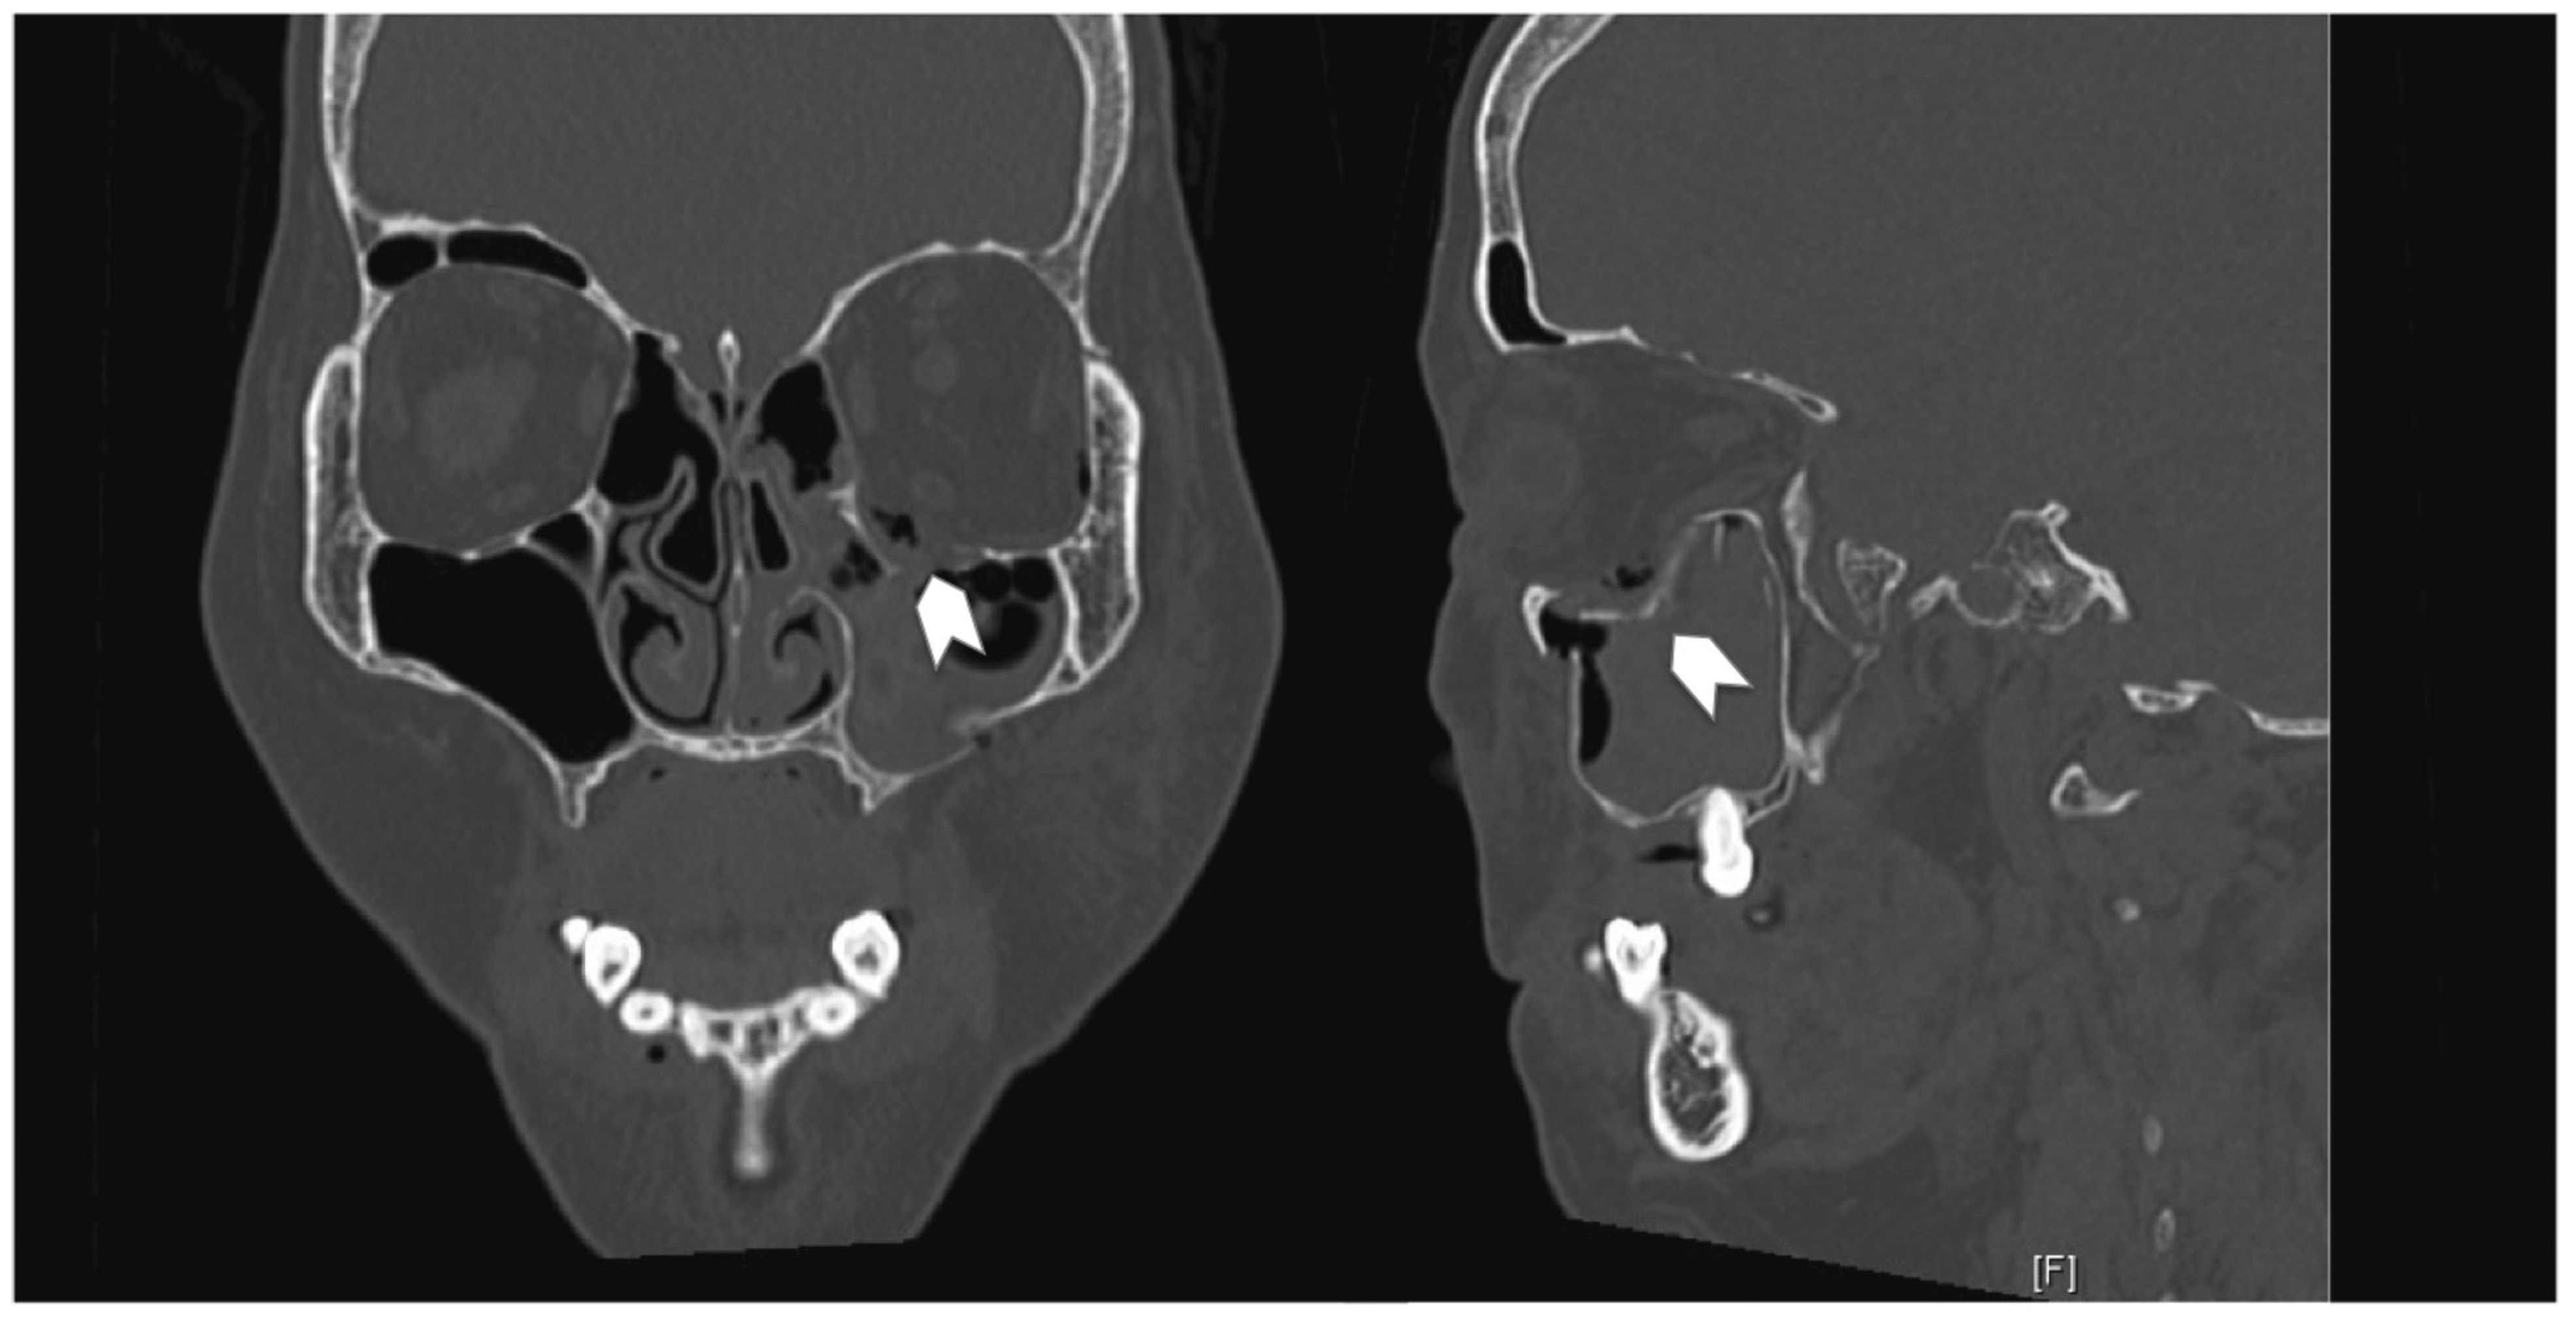

A 40-year-old man underwent an open reduction internal fixation (ORIF) of his right zygomaticomaxillary complex (ZMC) fracture and orbital floor reconstruction for a right orbital floor fracture, sustained after a road traffic accident (Figure 1). He had no preoperative diplopia.

The surgery took place 10 days following the accident due to neurosurgical concerns regarding his brain injury. Intraoperatively, the periorbita surrounding the herniated contents was noted to be disrupted. A 0.4-mm titanium curved plate was used to reconstruct the orbital rim, and the medium 0.4-mm precontoured titanium orbital plate (Figure 2) was used for reconstruction of the orbital floor defect (DePuy Synthes, Johnson & Johnson, Solothurn, Switzerland). Intraoperatively, he had a negative forced-duction test and postoperatively, he was noted to have full range of extraocular movements of his right eye. The postoperative CT scan demonstrated anatomical placement of the orbital floor plate with reduction of all periorbita (Figure 3).

Figure 1. Coronal and sagittal cuts of the CT scan of the face (Case 1) demonstrating the presence of a large right orbital floor defect (arrows).